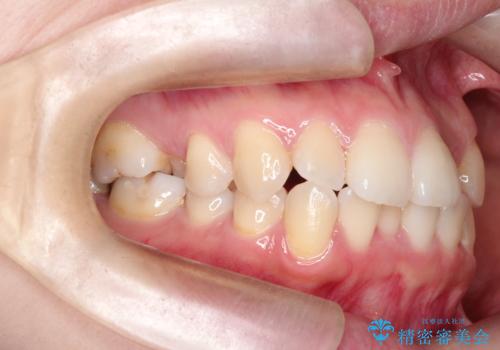

- 主訴:口元を下げて前突感を無くしたい、下の歯の凹凸も無くしたい

右側第二小臼歯、左側第一小臼歯、下顎両側第一大臼歯を抜歯しワイヤ-矯正を行いました。

骨格的顎の変位を認めたため、顔貌に対しピッタリ上下の歯の正中を合わせることは難しいと説明し、上下左右計4本小臼歯を抜歯しワイヤー矯正治療を行いました。